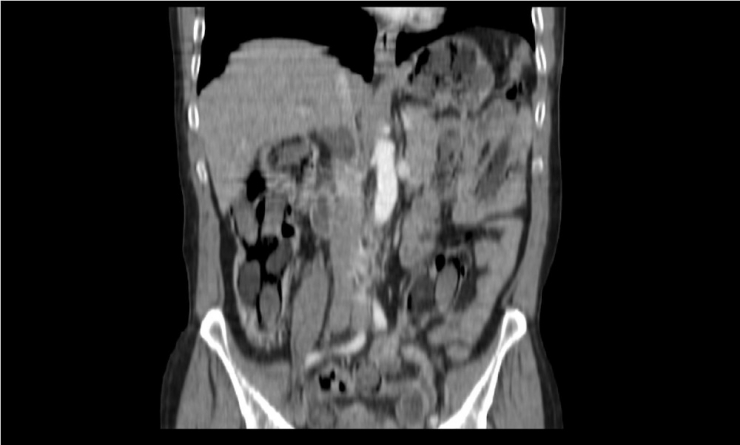

Polis, şahsın midesinde eroin olabileceğinden şüphelenip hemen hastanenin gastroenteroloji bölümüne götürdü. Burada tomografisi çekilen midede, sosis büyüklüğünde paketler tespit edildi. Ancak polis, emin olmak için daha sonra şahsa endoskopi işlemi de yaptırdı. Bu sayede ucunda ışıklı küçük bir kamera bulunan ve endoskopi adı verilen bir cihaz yardımıyla şahsın yemek borusu, mide, onikiparmak bağırsağı ve kalın bağırsaklarında 49 paket sosis büyüklüğünde paketler olduğu kesinleşti.